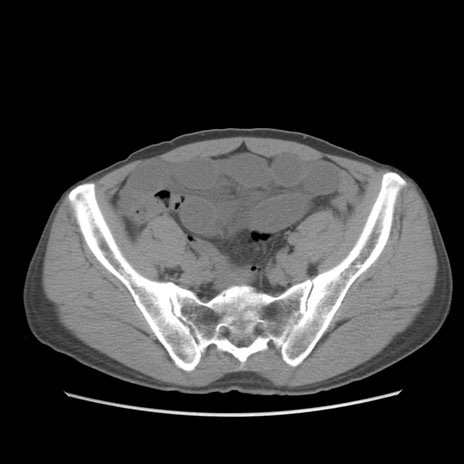

症例56 CT(横断像)

脂肪ウインドウ